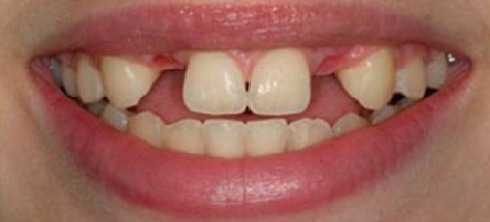

A 26-year-old female with severe crowding. Comprehensive orthodontic treatment was completed. Patients were amazed by the results.